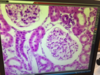

Kidney, silver impregnation